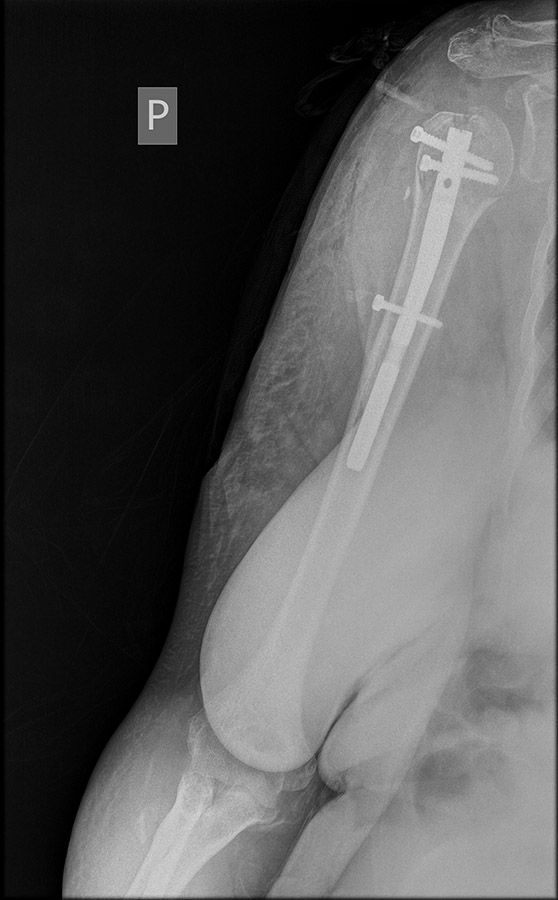

W przypadku złamań górnej części kości ramiennej, istnieje kilka technik, które można zastosować. Mogą to być szpilki, płytki ze śrubami, same śruby lub gwoździe (metalowe pręty). Istnieje również możliwość rekonstrukcji guzowatości kości, co jest szczególnie ważne w przypadku naprawy ścięgna mankietu rotatorów.

Każdy chirurg ma swoje preferencje i doświadczenie w zakresie wyboru techniki osteosyntezy. W niektórych przypadkach preferowane może być gwoździowanie śródszpikowe, gdzie wprowadza się gwoździe do głowy kości ramiennej i umieszcza się je w zagłębieniu trzonu kości strzałkowej. To pozwala na przymocowanie guzowatości do głowy kości ramiennej i trzonu za pomocą śrub oraz czasami szwów kostnych i ścięgnistych.